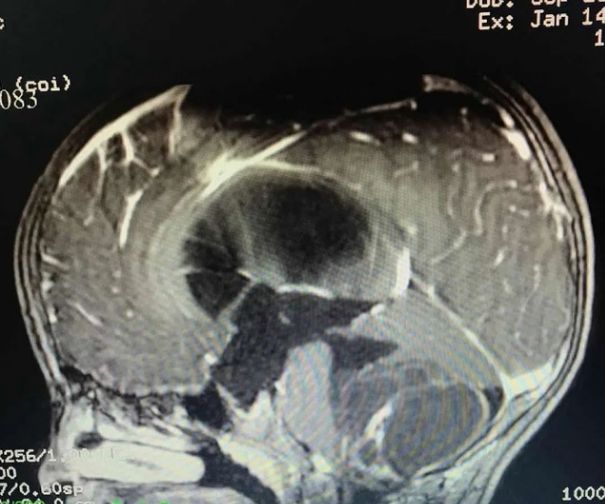

小乐手术前CT影像

根据小乐的既往病史、CT影像资料,该院对小乐进一步完善头颅MR检查,结果显示第四脑室右侧侧孔-桥小脑角区占位性病变,大小约48mm×38mm×35mm,呈一个鸡蛋大小。肿瘤已累及四脑室侧壁和顶壁,四脑室下部明显受压变窄,邻近脑干及小脑组织受压移位、变形。据悉,该院神经外科陈陆馗主任团队于1月16日为小乐进行“第四脑室及左侧桥小脑角区巨大占位切除术”,完整切除了肿瘤。手术顺利,病理诊断证实为毛细胞型星形细胞瘤(WHO1级)。目前,小乐恢复良好,术前的症状完全消失,于2月1日办理出院。随诊至今,精神、语言、肢体活动均无任何障碍。